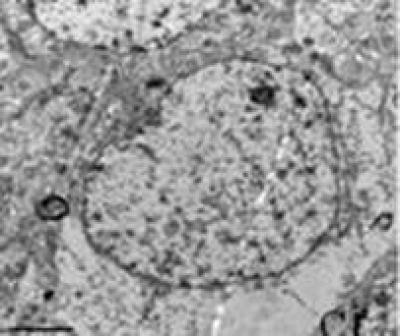

Dl-3n-butylphthalide can effectively treat cerebral ischemia; however, the mechanisms underlying the effects of dl-3n-butylphthalide on microcirculation disorders following diffuse brain injury remain unclear. According to a study by Prof. Jianmin Li and team from Hebei United University of China, models of diffuse brain injury were established in Sprague-Dawley rats with the vertical impact method, and dl-3n-butylphthalide at 80 and 160 mg/kg was given via intraperitoneal injection immediately after diffuse brain injury. After administration of dl-3n-butylphthalide, reduced cerebral ultrastructure damage, increased vascular density and cerebral blood flow, and improved motor and sensory functions were observed. These findings, published in the Neural Regeneration Research (Vol. 8, No. 28, 2013), demonstrate that dl-3n-butylphthalide may have protective effects against diffuse brain injury by ameliorating microcirculation disorder and reducing blood-brain barrier damage and cerebral edema.